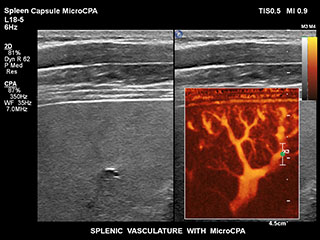

Получение информации о кровотоке в мелких сосудистых структурах с небольшим кровотоком традиционно считается сложной задачей. Благодаря новой функции MicroCPA в системе EPIQ визуализация капиллярного кровообращения с низкой скоростью кровотока выполняется быстро и просто, обеспечивая более точную диагностику при оценке перфузии органов и сети небольших сосудов.